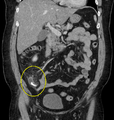

A fecolith marked by the arrow which has resulted in acute appendicitis.

Fecolith, also called a fecaloma or faecaloma, is an extreme form of fecal impaction, often characterized by calcification. The term fecalith literally means a "stone" made of feces (lith=stone). It is a hardening of feces into lumps of varying size and may occur anywhere in the intestinal tract but is typically found in the colon. It is also called appendicolith when it occurs in the appendix and is sometimes concomitant with appendicitis.[1] They can also obstruct diverticuli.